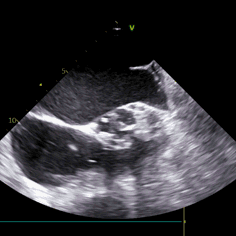

三叶瓣轻度钙化,右无可见钙化脊,瓣叶可见增厚,右冠高度可,左冠开口层面可见瓣叶,升主动脉未见明显扩张,法式窦及窦管交界稍小,两侧股动脉入路可,二尖瓣机械瓣置换术后。瓣环平均径23.7mm,LVOT26.8mm,STJ24.9mm,RCA18.4mm,LCA11.4mm。

2. STJ结构偏小且整体窦部结构不大,左冠瓣叶高度可达冠脉口,术中球囊预扩无造影剂下判断冠脉灌注情况难度大;

3. 全程无造影剂超声引导下行TAVI手术对超声团队高精度和快速判断要求极高,了解手术过程并同频配合术者手术操作,同时要求术者对超声解读深刻。